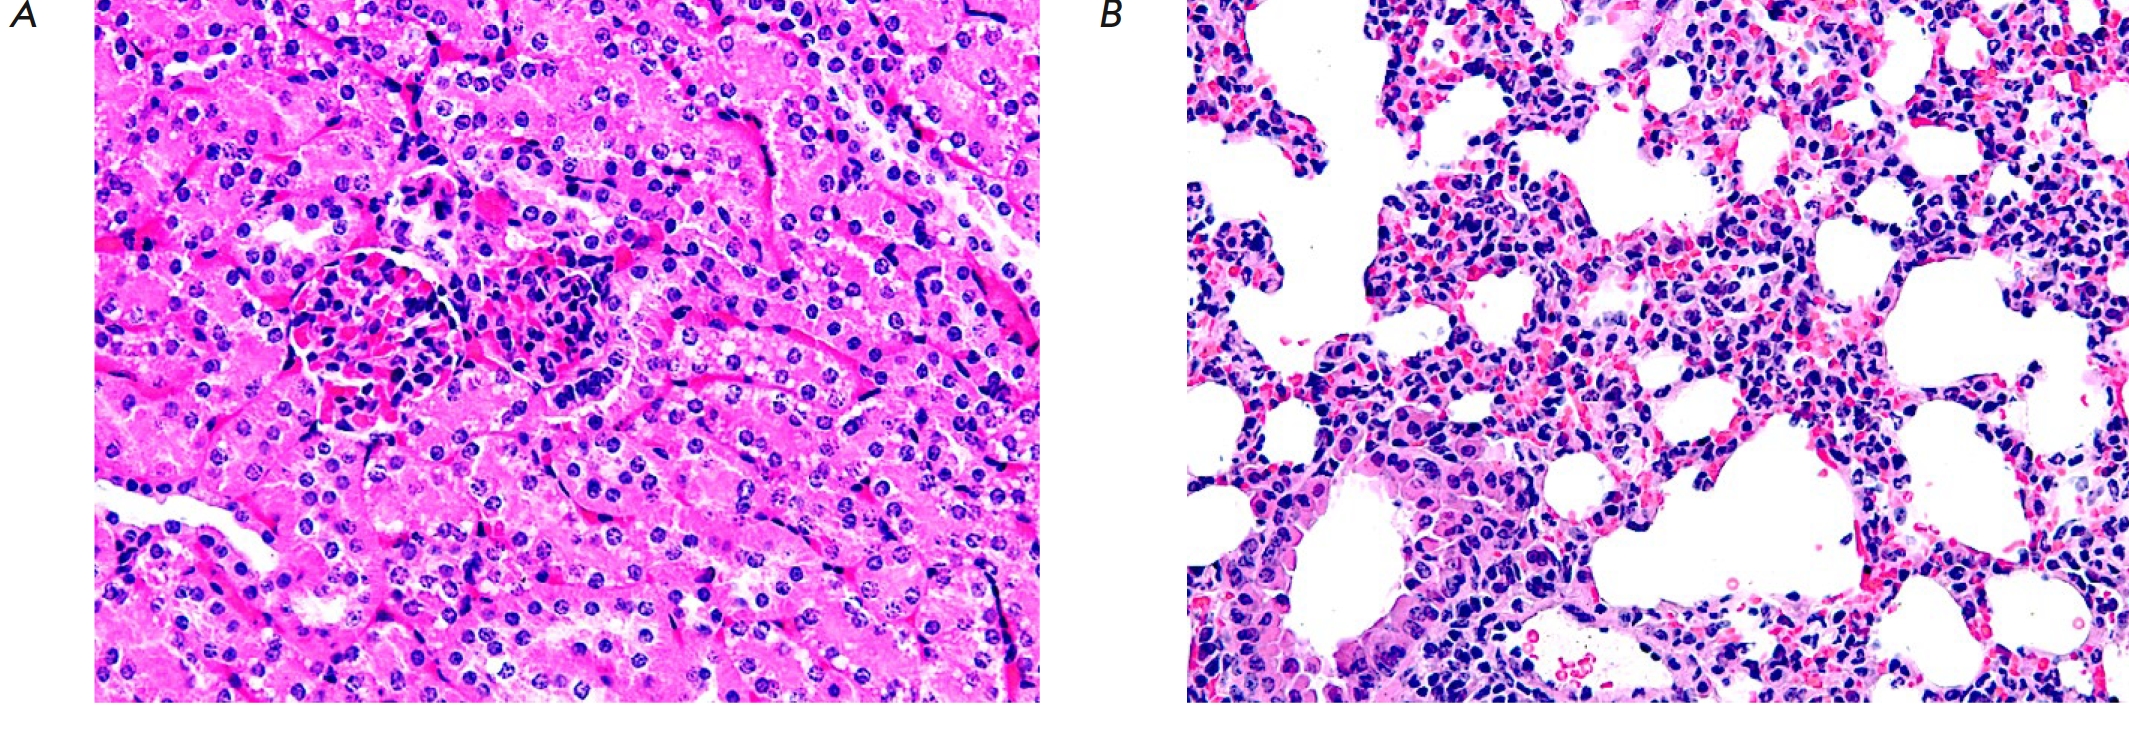

Fig. 2. A fragment of the mucous membrane of the wall of the stomach (A) and small intestine (B) in an experimental mouse after administration of 80 mg/kg 5'-noraristeromycin. Hematoxylin–eosin staining. 200× magnification

Administration of 5'-noraristeromycin at a dose of 80 mg/kg, which is close to the median lethal dose, to the animals induced pronounced changes in the histoarchitectonics of the analyzed organs and tissues. Hence, microscopic examination of the gastric wall revealed an activation of chief cells and mucoid cells, accompanied by gland dilation and accumulation of mucoid contents in them (Fig. 2A). Death and desquamation of numerous mucosal epithelial cells into the intestinal lumen was found when examining a small intestine fragment. The remaining villi became more flattened; their apical surface contained no fringe of microvilli. Thinning of the submucosa and partial reduction of the muscle and serous membranes were also observed (Fig. 2B).

Erythrocyte stasis and sludging in glomerular capillaries and the intertubular space were observed in the kidneys of an experimental mouse. The lumens of numerous convoluted tubules had narrowed, because of the hypertrophy of the epithelial cells lining them; the cytoplasm contained multiple vacuoles (Fig. 5A). Infiltration of the interstitial lung tissue by polymorphonuclear neutrophils was observed in the lung tissue of one experimental mouse. Alveolar septal thickening and edema, as well as erythrocyte diapedesis into interalveolar septa, were also detected (Fig. 5B).

Fig. 5. A fragment of kidney (A) and lung (B) tissue from an experimental mouse after administration of 80 mg/kg 5'-noraristeromycin. Hematoxylin–eosin staining. 400× magnification